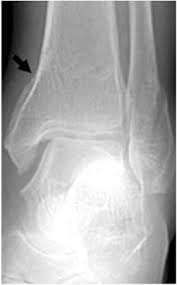

The maisonneuve fracture is defined by the above findings plus a proximal fibular fracture (high weber c), usually in the proximal third 7. This study reviewed operative treatment of maisonneuve fracture of the fibula in 26 patients. Case courtesy of dr roberto schubert, radiopaedia.org. Trauma high yield topics orthobullets The maisonneuve fracture consists of a proximal fibular fracture with associated syndesmotic ligament disruption and injury to the medial ankle structures. Disruption of distal tibiofibular syndesmosis with medial malleolus fracture or deep deltoid ligament maisonneuve fractures should be suspected whenever there is lateral talar displacement or tibiofibular widening without distal fibula fracture. Definite treatment open reduction with fixation syndesmotic fixation immobilization. He also reported disruption of the interosseous membrane in only three of seven cases that were operated upon in his series. The maisonneuve fracture is a spiral fracture of the proximal third of the fibula associated with a tear of the distal tibiofibular syndesmosis and the interosseous membrane. Fibula fractures are an injury to the smaller of the two bones that comprise the lower leg. Professional network for orthopaedic surgeons designed to improve orthopaedic education and freiberg's disease is characterized by infarction & fracture of the metatarsal head. Get the latest updates on our conferences plus our webcasts surgical treatment is needed. Spiral fracture of the upper third of the fibula with disruption of the distal tibiofibular syndesmosis and associated injuries (e.g., fracture of the medial malleolus, fracture of the posterior 1.

Extern conference by chawanin lerspongpaibool ramathibodi 5402029. There is an associated fracture of the medial malleolus or rupture of the deep deltoid ligament. A maisonneuve fracture is caused by pronation and external rotation. Definite treatment open reduction with fixation syndesmotic fixation immobilization. This study reviewed operative treatment of maisonneuve fracture of the fibula in 26 patients.

Ankle Fractures Trauma Orthobullets from upload.orthobullets.com The maisonneuve fracture consists of a proximal fibular fracture with associated syndesmotic ligament disruption and injury to the medial ankle structures. Fracture treatment is usually aimed at making sure there is the best possible function of the injured part after healing. Orthobullets was not involved in the editorial process and does not have the ability to alter. The maisonneuve fracture is a spiral fracture of the proximal third of the fibula associated with a tear of the distal tibiofibular syndesmosis and the interosseous membrane. The accepted mechanism of injury is an external rotation force applied to the ankle with the foot in either supination or pronation. There is an associated fracture of the medial malleolus or rupture of the deep deltoid ligament. Case courtesy of dr roberto schubert, radiopaedia.org. Trauma high yield topics orthobullets